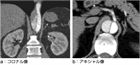

1. 180/120 mmHg以上の著しい高血圧では、予後の向上のために、早急に進行性の心血管系障害の有無を判断し、治療方針を確定すべきである(推奨度1)

1. 高血圧緊急症の症例を診察する際には、臓器障害を示唆する所見(胸痛、背部痛、呼吸困難、神経所見、けいれん、意識状態)の有無に注目する(推奨度1)

1. 血圧は両上肢で測定し左右差を確認する。眼底所見は高血圧緊急症の診断に有用であるため、確認すべきである(推奨度2)